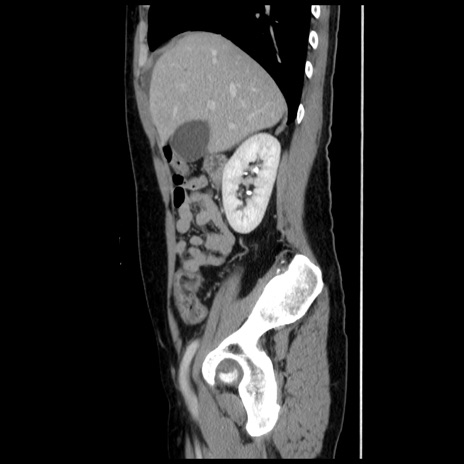

症例10(矢状断像)

【症例】 50歳代女性

【主訴】 腹痛

【現病歴】前日生レバーを食べた。今朝に排便あり。 昼前に突然発症の腹痛を生じ、当院救急外来を受診した。

【既往歴】 子宮筋腫にてで子宮全摘後

【身体所見】 意識清明、腹部:平坦、軟、下腹部やや左を中心に圧痛・反跳痛あり、筋性防御あり

【データ】WBC 7800、CRP 0.07